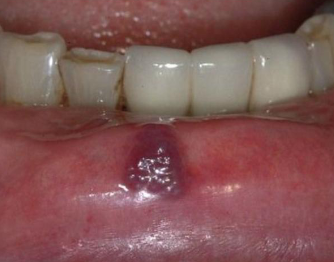

kaposi sarcoma

AIDS related vascular malignant neoplasm